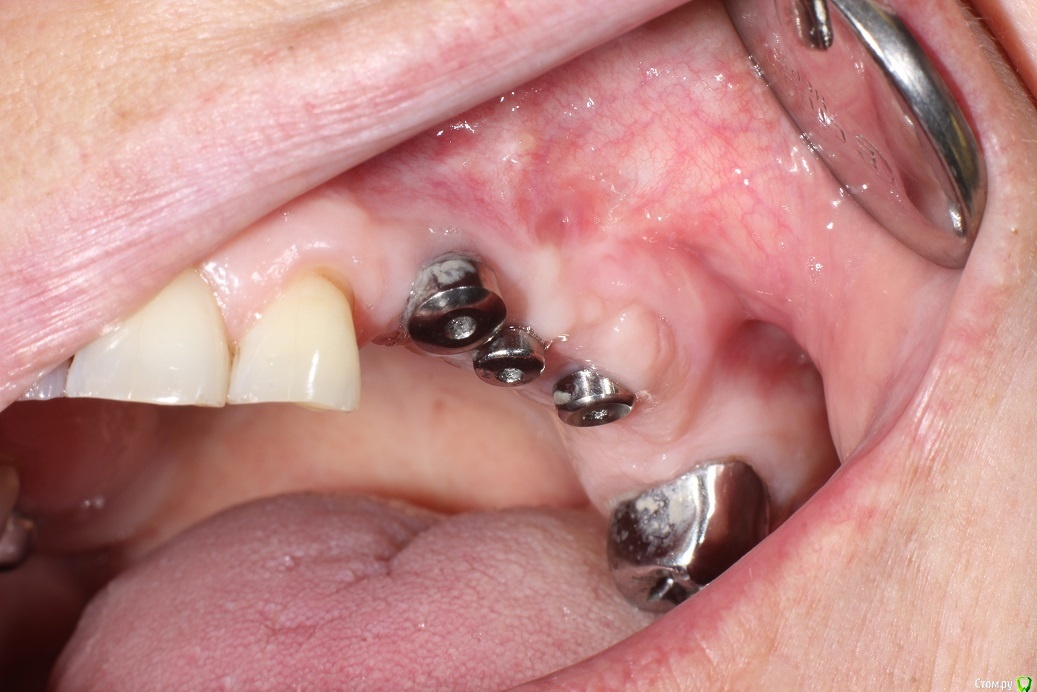

kuziy12 Опубликовано 2 ноября, 2020 Поделиться Опубликовано 2 ноября, 2020 Имплантация с синус лифтингом. Беда с позицией 2.3. Коронки на cad\cam, наносил розовую керамику и красил все сам. Сваливать не на кого) До: После имплантации: Формики: Десна: Постоянная конструкция: Улыбка: 3 Ссылка на комментарий

kuziy12 Опубликовано 3 ноября, 2020 Автор Поделиться Опубликовано 3 ноября, 2020 Шаблончики делайте)Начальству говорю - покупайте КТ. Не хотят гады. 2.6 консольный получился?да Это Вы уже импланты ставите? Умничка!А что за система, небось Ирис? MIS SEVEN Ссылка на комментарий

kuziy12 Опубликовано 9 октября, 2021 Автор Поделиться Опубликовано 9 октября, 2021 Дабы не плодить темы, выложу тут. Докрутил пациента полностью)) Ортопедия тоже моя. От переустановки импланта в области клыка отказалась. Ссылка на комментарий